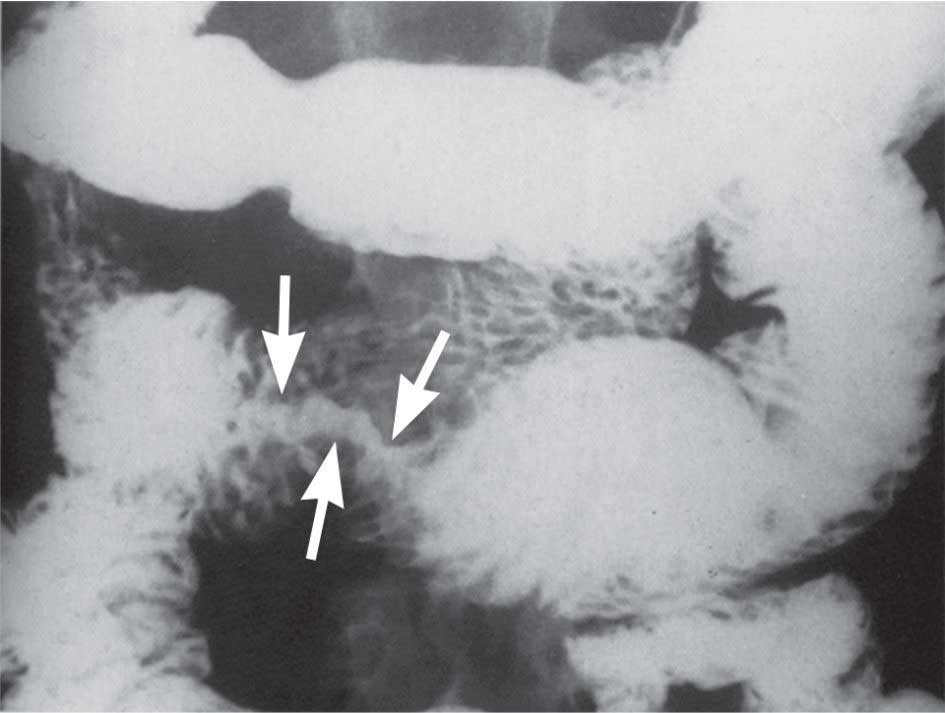

| الشكل (2) سرطانة غدية حلقية الشكل في الأمعاء الدقيقة (الأسهم) |